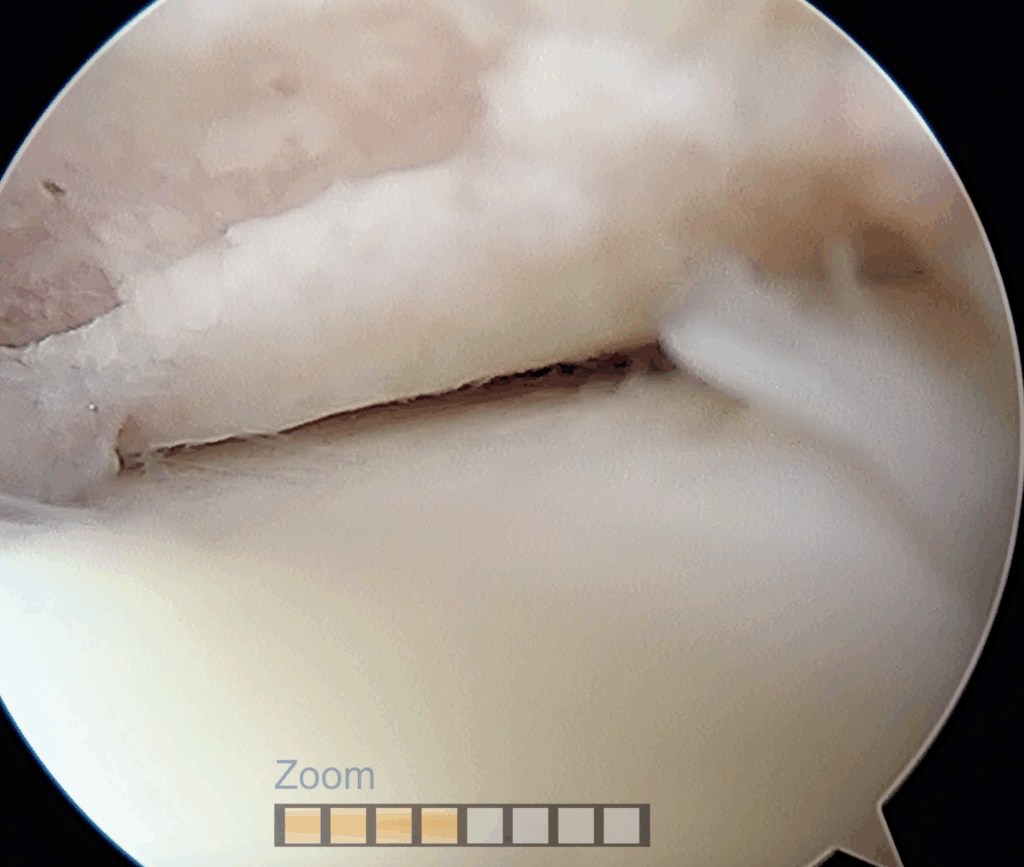

Particolarmente utile risulta essere nelle sindromi da “impingement”, ovvero in quelle situazioni in cui si crea un conflitto fibroso che rende doloroso e limitato il movimento. Questa situazione clinica è molto frequente negli esiti di fratture, soprattutto quelle trattate chirurgicamente in cui il danno articolare quasi sempre presente (fino all’80%) può evolvere in una vera e propria degenerazione artrosica di tutta l’articolazione.

Il danno cartilagineo quando ben limitato, può essere contenuto proprio grazie a procedure artroscopiche specifiche; anche in questo caso le opzioni terapeutiche, anche grazie alle nuove tecniche innovative proposte negli ultimi anni, sono molteplici e l’accurata selezione del paziente, con un dettagliato planning personalizzato ci permette di scegliere il miglior trattamento possibile.

In questi casi, nelle lesioni più piccole, è possibile rimuovere frammenti di cartilagine e stimolare il tessuto osseo spongioso con microperforazioni; in quelle superiore a 1,5 cm2 è possibile rimuovere frammenti cartilaginei, effettuare microfratture per stimolare la rigenerazione del tessuto osteo-cartilagineo. È possibile inoltre eseguire degli innesti di tessuto mesenchimale da tessuto adiposo o con matrice autologa, sempre per via artroscopica, con l’obiettivo di riempire la perdita di sostanza, ottenendo la risoluzione, o il miglioramento della sintomatologia e della funzionalità della caviglia.